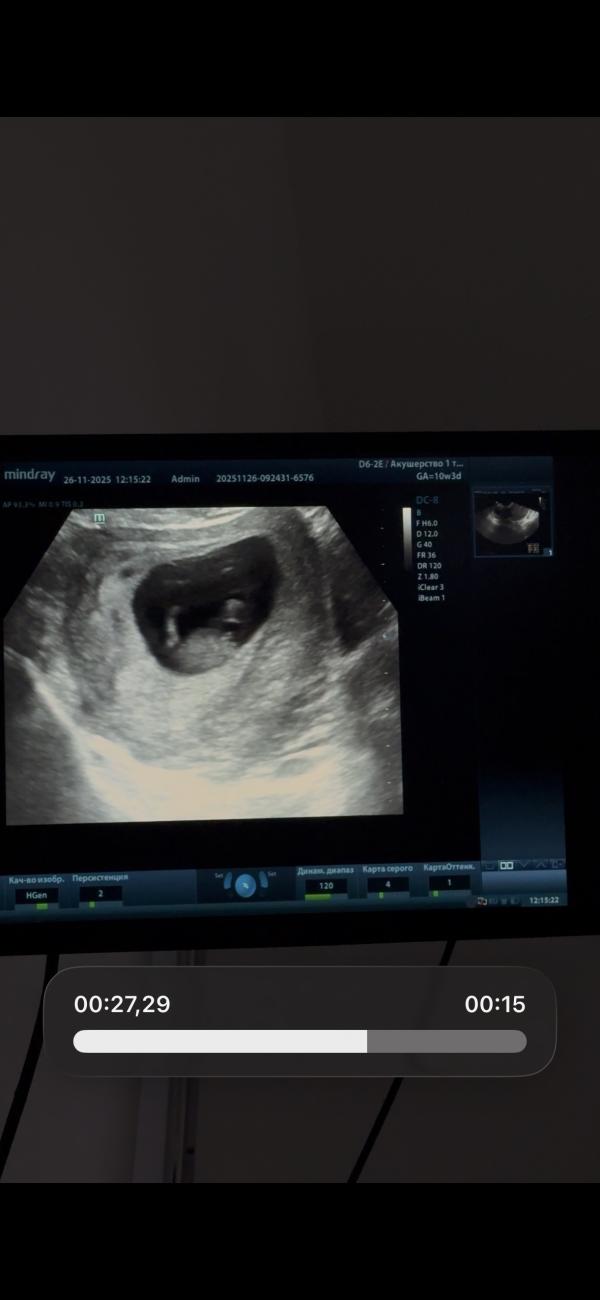

Полистайте карусель

И скажите

Мальчик это или девочка

😂

Тут не может быть ещё никаких яичек, тут тока бугорок, и то ещё рано судить, он может ещё подняться

@leyla.isl, ну в 10 недель яичек и писюна прям видно не будет по любому 😀